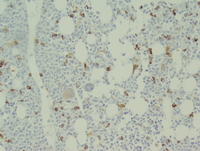

Bone marrow core biopsy

The bone marrow is usually hypercellular. Dysplastic megakaryocytes are frequently seen. CD34 immunohistochemical stain can be helpful in the identification of blasts on the bone marrow core biopsy.